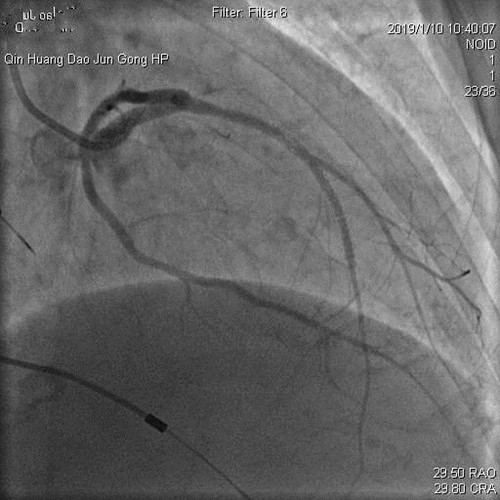

2019年1月10日,心内科王春梅主任、王嘉玮主治医师与北京安贞医院李昭教授共同完成首例冠脉支架内再狭窄药物球囊扩张术。手术的成功,对心内科介入手术的开展和医疗技术的提升具有重要意义。

患者杨某,女,74岁,因发作性胸闷到军工医院就诊。患者曾先后在某医院经冠脉植入过4枚支架及心脏永久起搏器,但是胸闷症状仍然没有解除。因杨某高龄、反复心梗、心衰,咨询多家医院均表示仅能药物保守治疗,拒绝为其行介入治疗。患者家属携带既往病历资料来军工医院咨询,心内科主任王春梅详细询问病情,积极与北京安贞医院李昭主任联系,详细查阅患者既往病历影像资料,考虑患者目前胸闷症状为前降支支架内再狭窄所致,有多次狭窄病变(病历资料显示狭窄病变为前降支两枚支架连接处的狭窄,既往因连接处狭窄已通过重叠植入支架治疗)。

王主任考虑患者高龄,反复心梗,心功能差,手术风险高,难度大。患者前降支血管承担着几乎整个心脏的供血,再狭窄部位为前降支的关键位置,如果手术过程稍有不慎,将会危及生命,后果将不堪设想。

经过反复沟通,向患者及家属详细讲解手术过程、风险及并发症。家属对军工医院表示信任,同意使用药物球囊治疗狭窄病变。经过近1小时的手术,成功为患者放入了药物球囊。出院2周后医生随访,张某病情平稳,无胸闷、胸痛症状。患者和家属对军工医院心内科王春梅主任勇于担当和技术精湛的医生团队表示感谢。